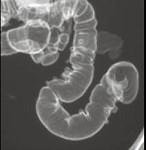

男,52岁,习惯性便秘2年余,结合图像,应诊断为 ( )A、结肠息肉病B、结肠转移瘤C、结肠憩室病D、假膜性结肠炎E、溃疡性结肠炎

问题 男,52岁,习惯性便秘2年余,结合图像,应诊断为 ( )

选项 A、结肠息肉病 B、结肠转移瘤 C、结肠憩室病 D、假膜性结肠炎 E、溃疡性结肠炎

答案 C